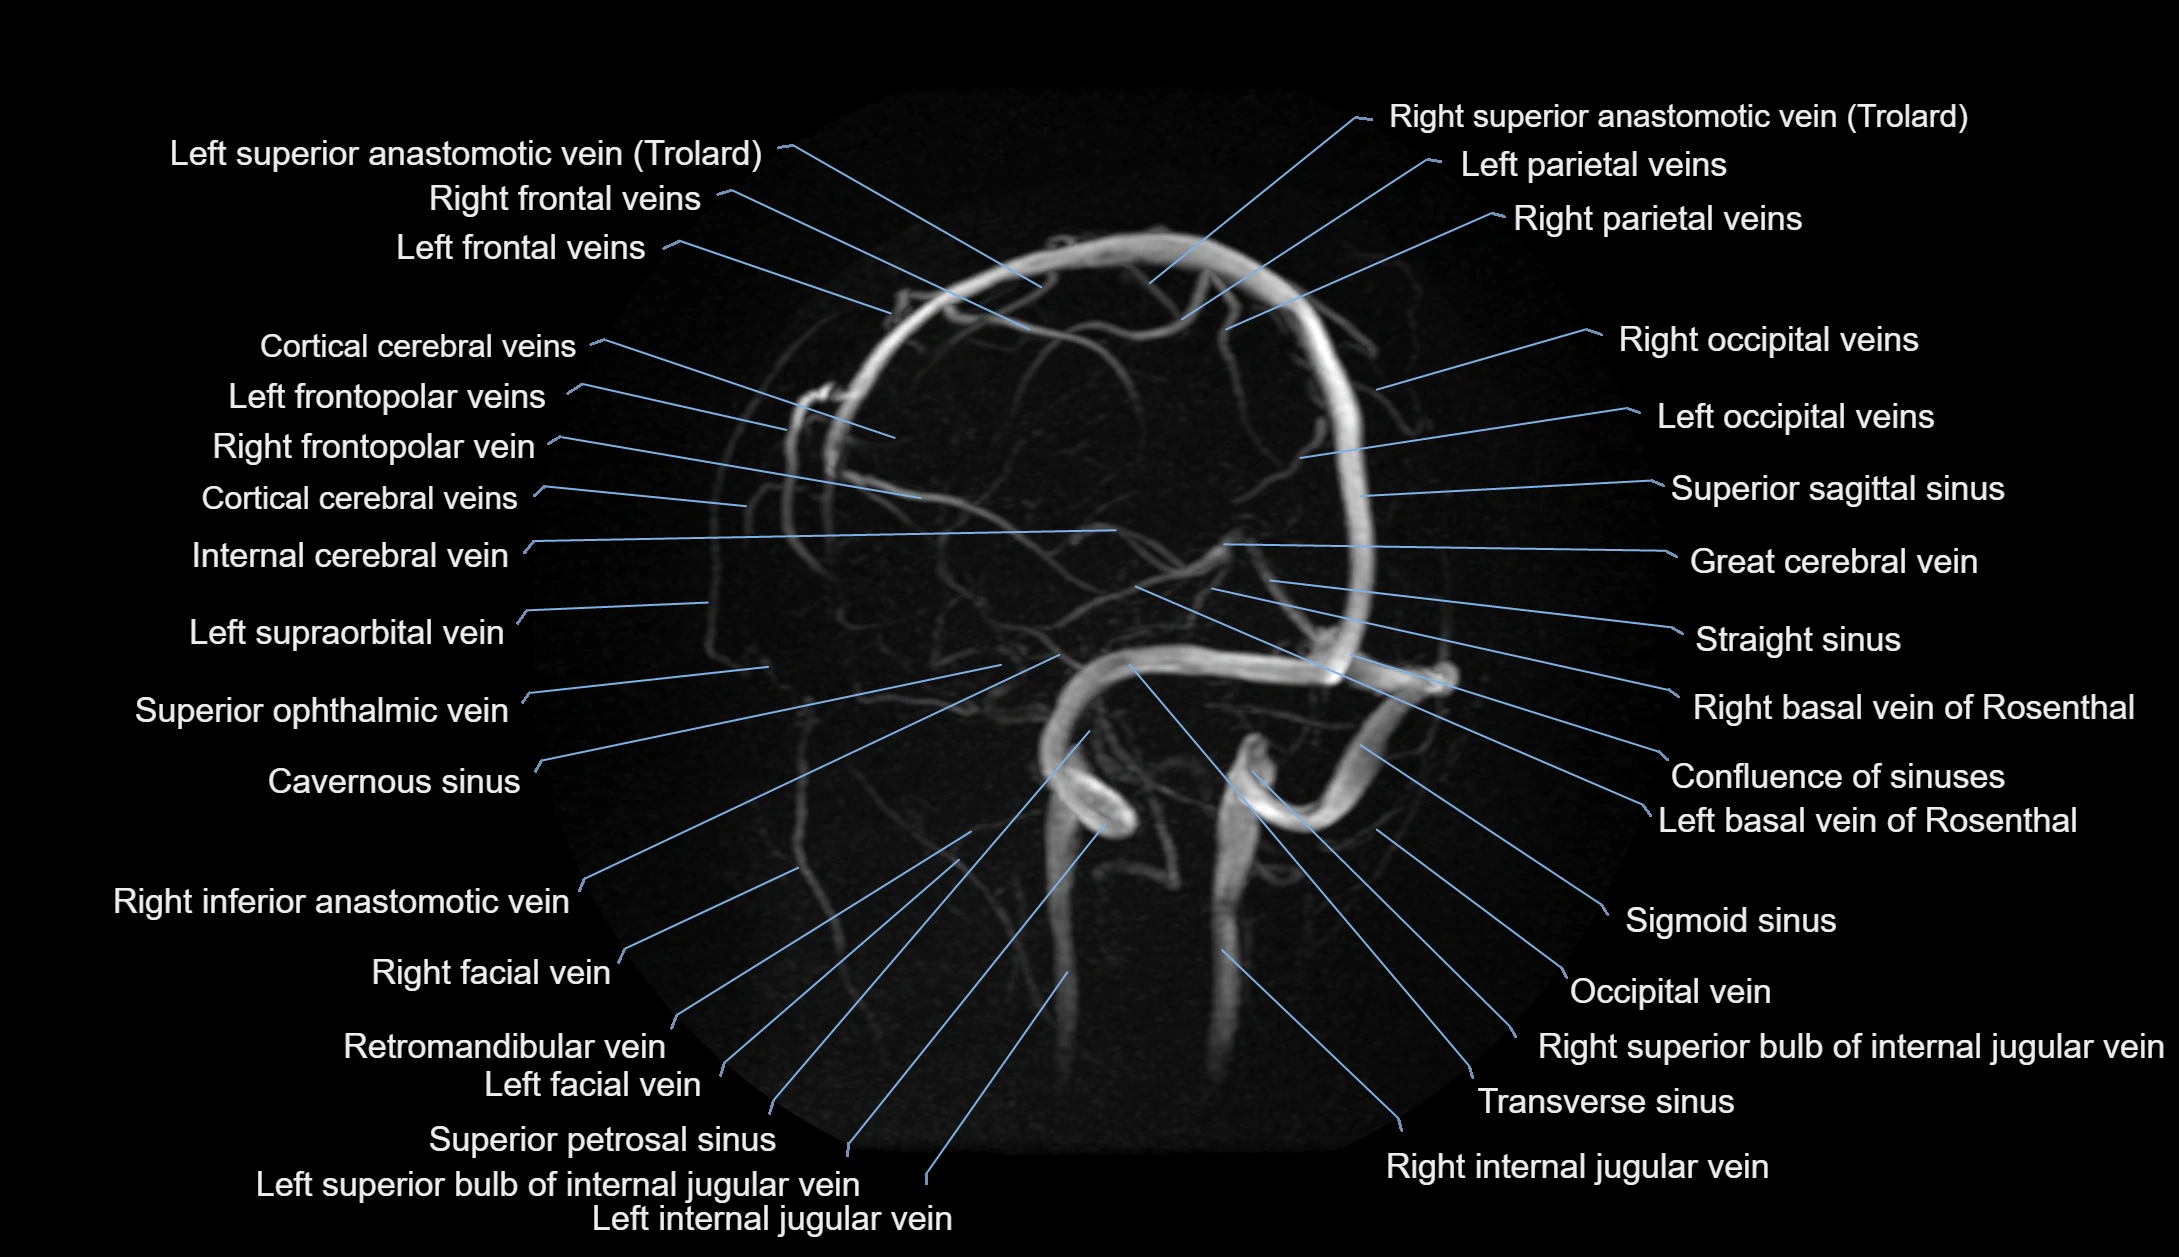

MR Venography (MRV):

• Time-of-flight (TOF) or contrast-enhanced MRV shows the angular vein as a bright enhancing venous channel

• Clearly demonstrates its continuity with the facial vein and superior ophthalmic vein

• MRV is highly useful in evaluating thrombosis, venous obstruction, or collateral venous drainage